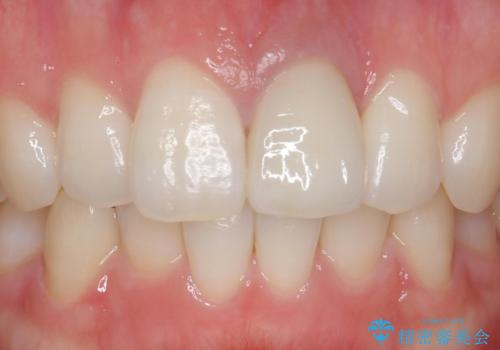

周囲の歯との色調に調和した審美的なクラウンを装着することができました。

歯茎の状態も良く、とても良い仕上がりになりました。